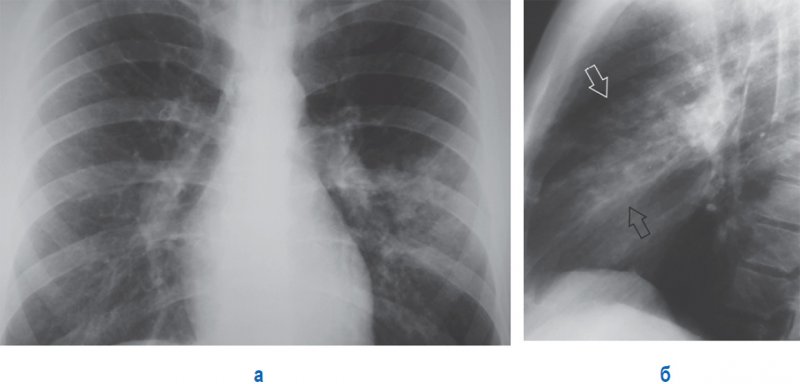

Полисегментарная (билобарная) правосторонняя плевропневмония

Рисунок 1. Полисегментарная (билобарная) правосторонняя плевропневмония.

А – в нижней и верхней долях справа отмечается распространенная однородная инфильтрация. Объем правого легкого уменьшен (это определяется по незначительно высокому положению купола диафрагмы справа и незначительному смещению трахеи вправо)

Б – увеличенный фрагмент рентгенограммы в прямой проекции. В – рентгенограмма правой боковой проекции. В нижней и верхней долях правого легкого определяется однородная распространенная инфильтрация. Отмечается утолщенная горизонтальная междолевая плевра. Стрелками обозначены видимые на фоне инфильтрации просветы бронхов – симптом «воздушной бронхографии»